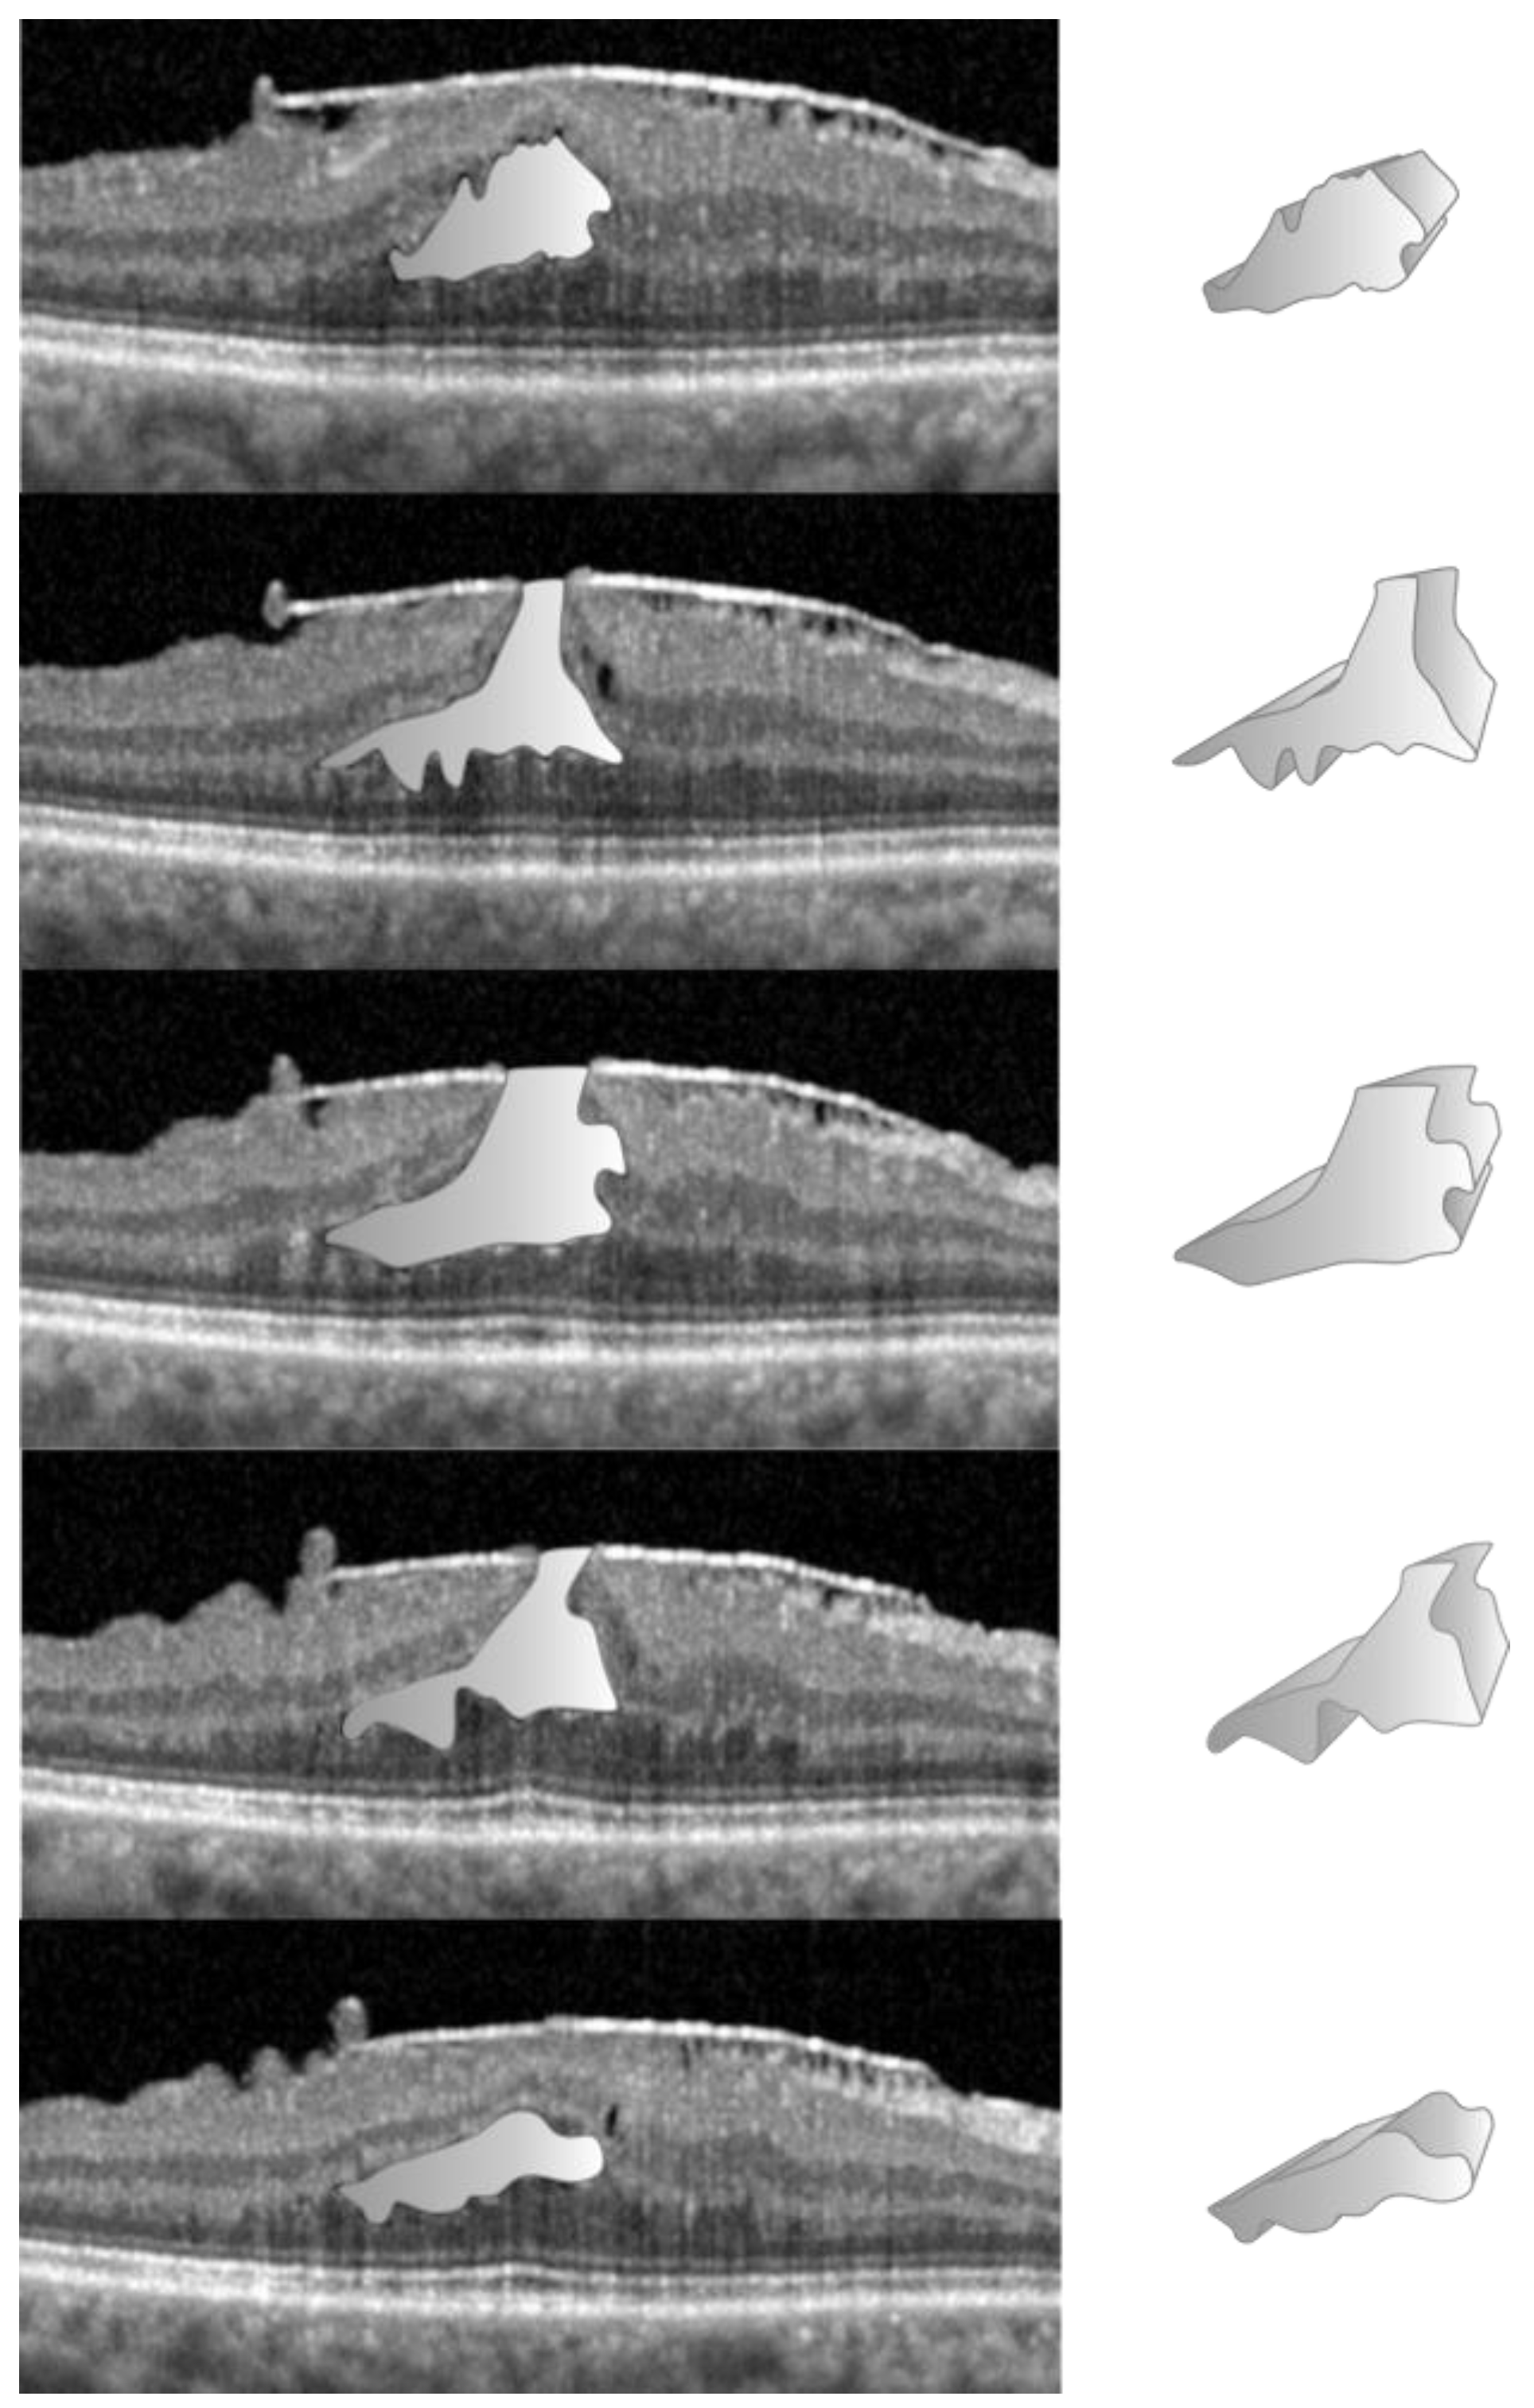

2.3. Data Acquisition in the LMH Group

- Lippera, M.; Moussa, G.; Ivanova, T.; Ferrara, M.; Spiess, K.; Ally, N.; Jasani, K.; Dhawahir-Scala, F.; Patton, N.; Jalil, A. Volumetric Biomarkers of Visual Outcome after Surgical Repair in Lamellar Macular Holes. J. Pers. Med. 2024, 14, 755. [Google Scholar] [CrossRef] [PubMed]